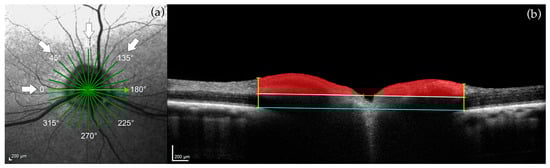

2.3.1. Optic Nerve Head (ONH) Measurements

3.1. Optic Nerve Head

| Myelin peak height | 0° | 154 +/− 38.4 μm | 9.3 +/− 22.1 μm | 0.010 | −0.78 | 0.003 |

| 90° | 119 +/− 30.9 μm | 24.0 +/− 17.7 μm | 0.026 | −0.57 | 0.05 |